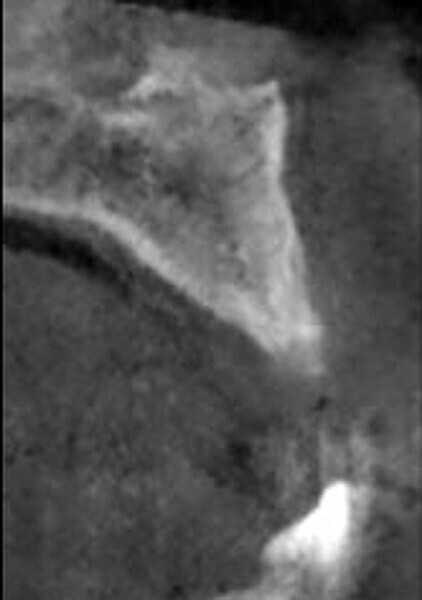

Fig. 2: CBCT cross-section demonstrating insufficient ridge width facial-palatally to permit implant placement in the healed extraction sites.